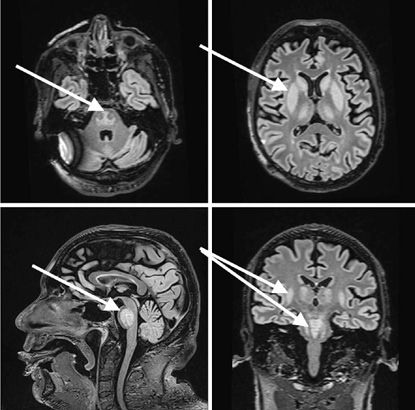

Upon arrival at the ED, the patient’s vital signs were: blood pressure 147/99 mmHg, heart rate 90 beats per minute, respiratory rate 17/min, oxygen saturation 95%, body temperature of 36.2 °C, and Glasgow Coma Scale (GCS) value 10 (the patient spontaneously opened his eyes, was nonverbal, and localized the pain he was experiencing). Pupils: Symmetric and photoreactive. Bulbar symptoms were observed, with excessive salivation and choking. The patient muttered indistinct sounds, did not respond to questions, and failed to follow commands. Notable extensor tone was observed in the extremities, which was more pronounced on the right side than on the left. The pathological Babinski reflex was present on the right. A head CT was performed again, confirming no signs of cerebrovascular issues or hemorrhage. The patient was admitted to the Neurology Department for further investigation, suspecting and trying to differentiate between Posterior Reversible Encephalopathy Syndrome (PRES), vertebrobasilar stroke, or neuroinfection. In the Neurology Department, the patient developed a fever up to 39.2 °C, and a respiratory failure started to progress. Multiple tests were run in the department. A lumbar puncture (glucose 3.87mmol/l, [2.2–3.9], protein 0.50g/l [0.15–0.45], cells 0 x 10^6 /l, white blood cells 0x 10^6 /l) showed no signs of neuroinfection. An electroencephalogram (EEG) was performed, and its results showed no epileptiform changes. A brain MRI was performed under general anesthesia to differentiate between ischemic and hemorrhagic changes, prion disease, PRES syndrome, and inflammatory changes. During the MRI, the patient was intubated; however, due to an ongoing severe respiratory failure requiring mechanical ventilation, the patient was transferred for further treatment to the Neurosurgery Intensive Care Unit. Upon arrival at the Neurosurgery Intensive Care Unit (NICU), the patient had a GCS of 3, with pupils equal and photoreactive. Consciousness was assessed in the context of sedation and muscle relaxants. The patient was on mechanical ventilation, with SpO2 levels between 88–90%. Hemodynamics were stable, with a heart rate of 128 bpm, and a blood pressure of 160/107 mmHg. The capillary refill time was 5 seconds, and his body temperature was 38.7°C. The predominant issues were a severe respiratory failure, an unclear neurological diagnosis, and an uncertain infectious status. Treatment was provided with crystalloids infusion therapy and correction of homeostasis, the patient was sedated with propofol and fentanyl, low molecular weight heparin was given for thromboprophylaxis, thiamine 500 mg three times daily, and magnesium sulfate 25% (to rule out Wernicke’s encephalopathy). Since the CRP and leukocytosis were growing, multiple tests were performed to identify the infectious agent. Blood, bronchial secretion, and urine cultures were taken. Respiratory virus detection tests were taken, as well as antibodies against Treponema pallidum, Human Immunodeficiency Virus (HIV), Herpes Simplex, Borrelia burgdorferi, tick-borne encephalitis, and Epstein-Barr Virus (EBV). MRI Findings showed that a markedly hyperintense area was noted in the mid-dorsal portion of the brainstem on T2-weighted images, with signs of diffusion restriction and no pathological contrast enhancement. Symmetrical, homogeneous T2-weighted hyperintensities were seen in areas around the caudate nucleus, lentiform nucleus, internal capsule (more pronounced dorsally), thalamus, and amygdala, without clear diffusion restriction or pathological enhancement (Figure 1). The MRI findings suggested possible extrapontine and pontine myelinolysis. Liver enzymes and ammonia were within normal limits, as were thyroid hormones and vitamin B12 and folate levels. Respiratory virus detection tests came back negative, as well as antibodies against Treponema pallidum, HIV, Herpes Simplex, Borrelia burgdorferi, tick-borne encephalitis, and EBV. The patient was treated in the Neurointensive Care Unit for 5 days due to coma and respiratory failure caused by acute demyelinating syndrome (osmotic myelinolysis). Given the clinical progression and observed changes, the prognosis was deemed unfavorable. Following neurological recommendations and current literature, a methylprednisolone pulse therapy was initiated, as there was no specific treatment available. Although, no evidence for autoimmune encephalitis was found. A test for antibodies against neuronal surface antigens came back negative. The condition was complicated by septic shock with multiple organ dysfunction syndrome, with a potential infection source in the lungs (the CRP value was 127 mg/l). Broad-spectrum antibiotics tazocin (4.5g; 4/day) and vancomycin (started with 2g with an automatic syringe pump) were administered as the decision was made to treat it as a septic shock with an unknown infection source. Following the methylprednisolone pulse therapy, leukopenia and neutropenia emerged. Sedation was discontinued, and the patient remained with a GCS score of 3. Throughout treatment, the patient’s condition remained very critical, with a worsening trend. Consciousness remained at GCS 3 under sedation, with continued need for mechanical ventilation and vasopressors, whereas septic shock was progressing. By the end of day five, a diminishing cardiac activity was observed, leading to asystole. Resuscitation efforts were initiated according to adult protocols. In the absence of cardiovascular response to resuscitation, the patient was pronounced dead. The patient’s relatives refused the autopsy.